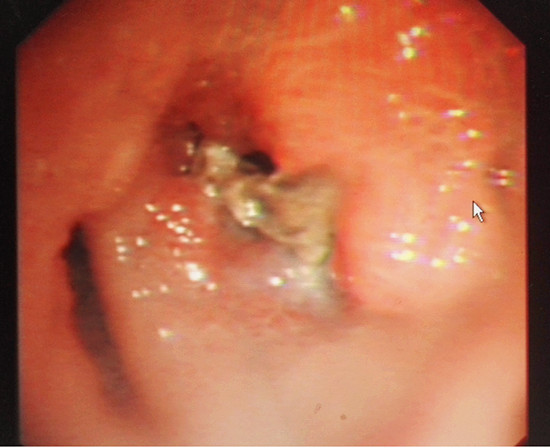

(电子支气管镜下见异物嵌塞,肉芽生长包绕异物)

由于异物停留时间长达半年,范发才主任透过纤支镜发现,谢先生的气管已扭曲变形,肉芽生长包绕着异物,异物钳取难度非常大。但大家并没有气馁,凭着过硬的专业技术紧紧夹住异物一毫米一毫米往外带离气管,在大家期待的目光中,停留半年之久的“不规则硬骨头”终于脱离谢先生体内。当晚,谢先生的咳嗽症状明显改善,安睡了一个晚上。